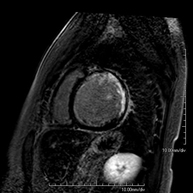

Es una prueba diagnóstica no invasiva que obtiene información morfológica y funcional del corazón y las estructuras adyacentes; de esta manera se pueden diagnosticar diferentes patologías congénitas y adquiridas, o bien realizar controles en pacientes con patología previa ya conocida. En la gran mayoría de casos es necesario el uso de contraste intravenoso (gadolinio) para completar el estudio, un tipo de contraste que raramente produce reacciones adversas. Durante la prueba, el técnico le pedirá varias veces que aguante la respiración durante 10-15 segundos para obtener las imágenes lo más claras posible. No se necesita preparación previa alguna por parte del paciente. La duración de la prueba es de aproximadamente 45-60 minutos. Está contraindicada en pacientes con marcapasos; el paciente debe avisar si es portador de implantes metálicos y/o clips quirúrgicos. - RM Cardíaca con estrés miocárdico

Es una prueba diagnóstica no invasiva, que obtiene información morfológica y funcional del corazón y las estructuras adyacentes. De esta manera, se pueden diagnosticar diferentes patologías congénitas y adquiridas, o bien realizar controles en pacientes con patología previa ya conocida. En la gran mayoría de casos es necesario el uso de contraste intravenoso (gadolinio) para completar el estudio, un tipo de contraste que raramente produce reacciones adversas. Durante la prueba, el técnico le pedirá varias veces que aguante la respiración durante 10-15 segundos, para obtener las imágenes lo más claras posible. No se necesita preparación previa alguna por parte del paciente. La duración de la prueba es de aproximadamente 45 - 60 minutos. Está contraindicada en pacientes con marcapasos, y el paciente debe avisar si es portador de implantes metálicos y/o clips quirúrgicos. - RM Cardíaca con estrés miocárdico